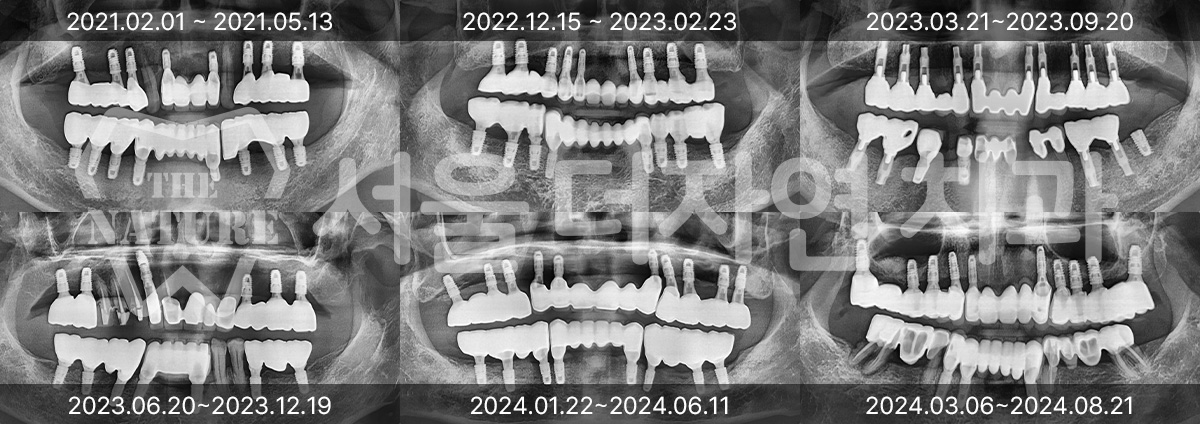

#Full Mouth Implants

-

BEFORE: 2022.12.15

AFTER: 2023.02.23

#Sinus Lift

BEFORE: 2021.02.01

AFTER: 2021.05.13

#Maxillary Bone Grafting

BEFORE: 2021.11.02

AFTER: 2022.01.19

Treatment outcomes may vary by patient,

and side effects may occur.

These images were taken under the same conditions,

and were published with the patient's consent.